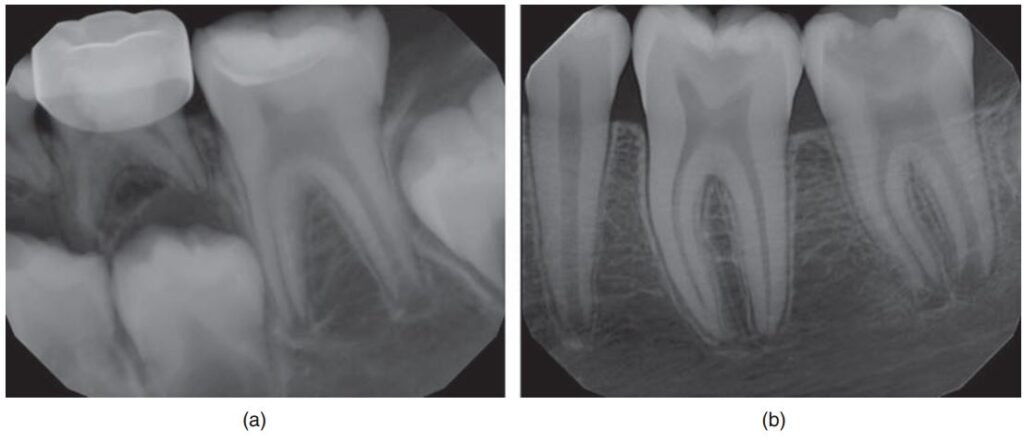

Thời gian để chân răng vĩnh viễn phát triển hoàn toàn là 3 năm kể từ khi mọc, do đó trước khi thực hiện bất kì thủ thuật điều trị tủy nào trên răng trẻ em cũng cần chụp phim, không những để loại trừ bệnh lí mô quanh chóp mà còn để kiểm tra sự đóng chóp của chân răng (H10.1).

Sau khi khám và đánh giá X quang kĩ lưỡng (H10.3) thì thực hiện gây tê, đặt đê (H10.4).